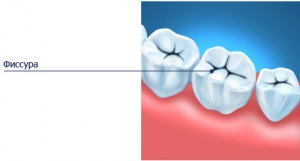

Crown parte în dinți înțelepciunea este specific Fisura de mestecat dinte.